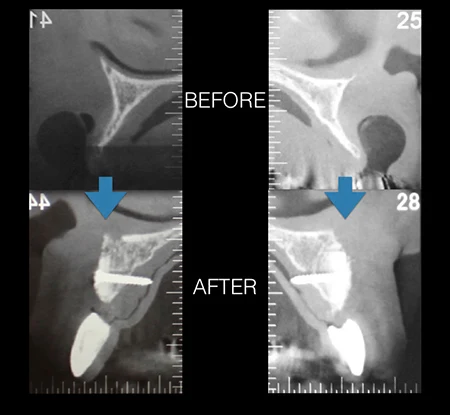

術前のCT画像。インプラントを入れられないくらい骨が痩せてしまっているためブロック骨移植によって骨の厚みを増やしてからインプラントの埋入をおこなうことになりました。

術前術後のCT画像。外側に骨のボリュームが増えているのがわかります。